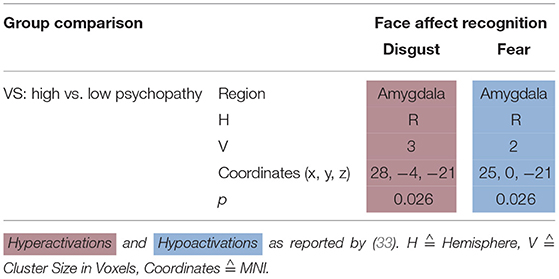

Face Affect Recognition

Dolan and Fullam (32) compared VS with high vs. low psychopathy using a face affect recognition task. When viewing a disgustful face, high psychopathy VS hyperactivated the right amygdala—when viewing a fearful face, they hypoactivated it (see Table 4).

Face Affect Recognition

Individuals with schizophrenia suffer from difficulties in recognizing emotional states (47). Persons with antisocial behavior also tend to show deficits in recognizing facial emotion expression with the amygdala being specifically involved in the processing of fearful facial affect (48). In the following, we will in detail disentangle the results of studies on face affect recognition in persons suffering from schizophrenia with vs. without aggression.

VS with high psychopathy scores hyperactivated right amygdala when viewing and identifying disgustful faces, but hypoactivated it when viewing and identifying fearful faces (32). HC activate their left inferior frontal gyrus when viewing fearful faces (49). A meta-analysis by Fusar-Poli et al. (50) integrated findings stating that healthy controls activated the amygdala when viewing happy, fearful, and sad faces. Angry and disgusted faces activated the insula (50).

Persons with schizophrenia react to emotional stimuli by exhibiting reduced activation in the amygdala but increased activation in other regions that are usually not associated with emotion (51). Literature reporting brain activation to facial expressions in psychopathic samples is sparse. However, Deeley et al. (52) examined brain function as individuals with psychopathy and healthy controls processed facial emotion. When viewing happy faces, both groups hyperactivated the fusiform and extrastriate cortices, but this increase was significantly smaller in the psychopathy group. When processing fearful faces, healthy controls hyperactivated their fusiform gyrus while the psychopathy group hypoactivated it (52). These findings are not in line with the reviewed findings by Dolan and Fullam (32)—due to many influencing factors like e.g., mere effect of disease, level of psychopathy, and others it is very difficult to interpret these differential activation patterns. One study reported no neural dysfunction in response to angry faces in children with conduct disorder (53). There are no reports of impairments in the recognition of anger in psychopathic samples (48) or in patients with schizophrenia and high psychopathy scores (54). One study reported reduced arousal ratings in response to angry faces in psychopathic women (55). Neural responses are modulated by anxiety (56) and psychopathic traits are associated with low anxiety levels (57). High psychopathy scorers exhibited increased amygdala response to disgustful faces. There are no published studies on disgust in psychopaths but there are reports that individual differences in disgust sensitivity moderate neural responses to disgust stimuli in HC (58, 59).

Synthesis of Findings From Studies Using Face Affect Recognition Paradigms

In Figure 3, we provide an overview on activation patterns during face affect recognition over all reviewed studies. In Figure 3A, VS show hyperactivation in the right amygdala in persons with high as opposed to low psychopathy scores when viewing facial expressions of disgust. To our knowledge, there are no previous studies on brain activation patterns of aggressive persons on disgustful faces, but it has been observed that more aggressive persons exhibit higher amygdala activation when seeing angry faces (15).

Figure 3. Face affect recognition activations. Overview of the working memory brain activation patterns reported by the reviewed studies in the group comparison VS high vs. VS low. Hyperactivations are shown in red, hypoactivations in blue. (A) Shows the activation patterns in the group comparison VS high vs. VS low with VS high>VS low in red showing the contrast of neutral vs. disgustful faces, (B) shows the activation patterns in the group comparison VS high vs. VS low with VS high<VS low in blue showing the contrast of neutral vs. fearful faces. Shown slice numbers are 100, 110, 120, 130.

When viewing fearful faces, as shown in Figure 3B, VS with high vs. low psychopathy hypoactivated the right amgydala. This is in line with findings reporting that persons with schizophrenia show hypoactivations of the amygdala in response to emotional stimuli.